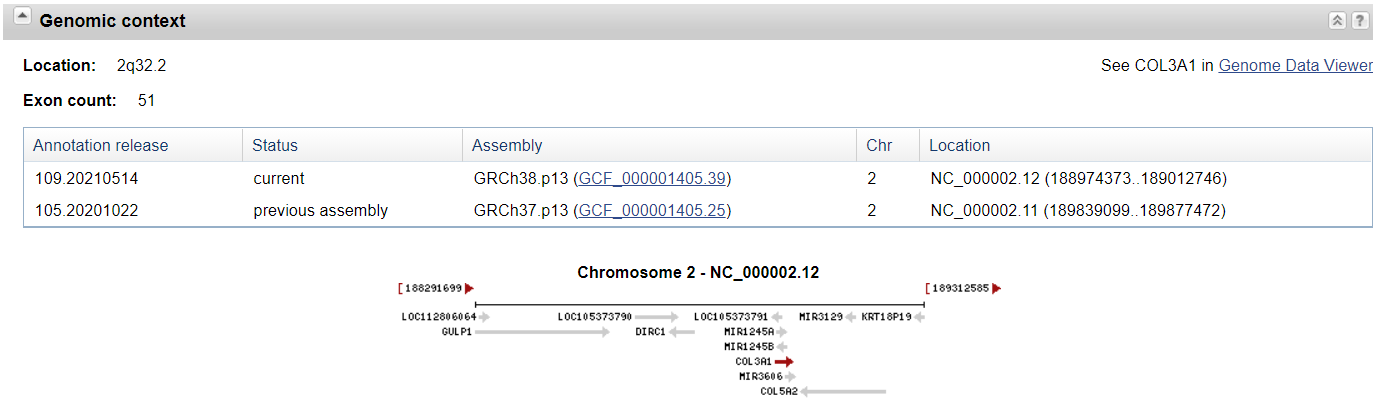

- COL3A1基因位于 2 2 2 号染色体的长臂 ( q ) (q) (q),位于 2 q 32.2 2q32.2 2q32.2 处,位置 188 , 974 , 372 188,974,372 188,974,372 和 189 , 012 , 745 189,012,745 189,012,745 之间。该基因有 51 51 51 个外显子,约 40 k b p 40 kbp 40kbp 长。COL3A1基因的尾巴方向与另一种原纤维胶原蛋白的基因,即COL5A2一致。